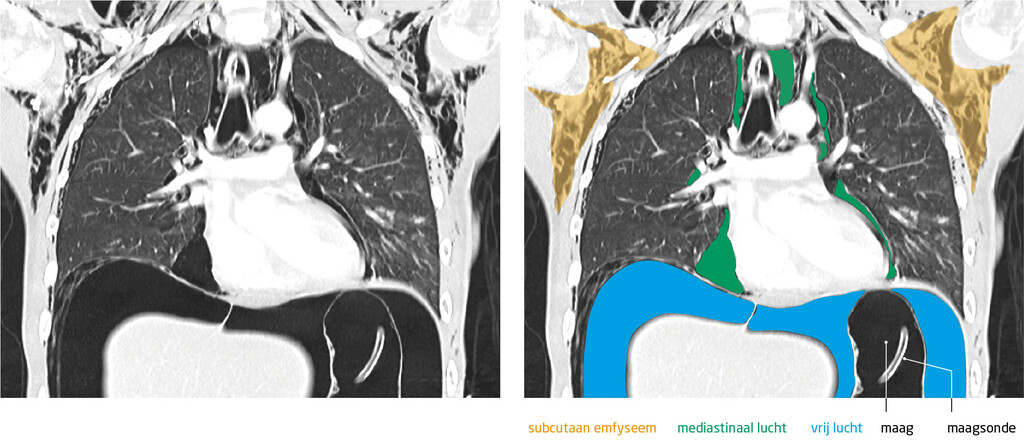

In de nacht trad klinische verslechtering op met hypotensie en een bolle, opgeblazen buik die bij percussie hypertympaan was. Daarom werd CT van de thorax en het abdomen verricht, waarop een fors uitgezette maag werd gezien met daarbij vrij lucht en vocht in de buik (figuur 1).

Figuur 1

CT van de patiënte met een maagruptuur

Figuur 1 | CT van de patiënte met een maagruptuur

CT van abdomen en thorax (coronale coupe) bij een patiënte met aanhoudende buikpijn en overgeven daags na een eetbui. Haar BMI was 15 kg/m2. De massale aanwezigheid van vrij lucht in de buikholte, lucht in het mediastinum en subcutaan emfyseem zijn suggestief voor een maagruptuur.